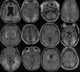

Posterior reversible encephalopathy syndrome

Posterior reversible encephalopathy syndrome (PRES), also known as reversible posterior leukoencephalopathy syndrome (RPLS), is a rare condition in which parts of the brain are affected by swelling, usually as a result of an underlying cause. Someone with PRES may experience headache, changes in vision, and seizures, with some developing other neurological symptoms such as confusion or weakness of one or more limbs. [Source: Wikipedia ]